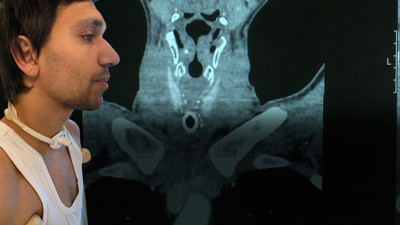

Geçirdiği kaza sonrası nefes borusu tamamen tıkanan genç mucize ameliyat ile sesine kavuştu Geçirdiği trafik kazası sonrasında yoğun bakımda kalan 25 yaşındaki Berkay Kaynak’ın nefes borusu tamamen tıkanmıştı. Nefes alabilmesi için açılan trakeostomi sonrasında ise sesini de kaybeden Kaynak'ı tekrar hayata döndüren geçirdiği zorlu ameliyatı oldu.